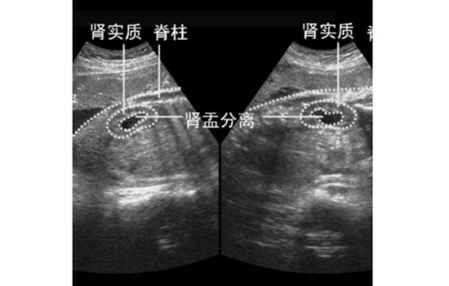

许多胎儿都有肾盂分离的问题,**们担心的是肾盂分离的胎儿出生后会不会有什么严重后果,其实如果胎儿是生理性的肾盂分离,出生后**就没事了,因为大多是因为憋尿导致的。但若是病理性的肾盂分离,治疗又不及时的话,那么后果是很严重的,不仅尿液无法正常排出,还会患上严重肾积水,所以应及早通过手术治疗。

胎儿肾脏有轻度分离是很常见的,一般来说,如果肾盂分离在10毫米以内,就是属于生理性的,这种情况不必担心,只需要定期复查B超就可以了。胎龄大于30周后肾盂扩张≥10毫米或存在肾小盏扩张,便称为肾积水,这种情况就属于病理性的。

一般来说,如果是病理性的,要在一个小时之后再进行复查,得出比较确切的**结果。如果复查结果,还是肾盂分离,就要医生进行进一步的**,这样的小宝宝出生后,进行积极的治疗,可以保证宝宝的肾功能在正常范围内。临床显示,产检发现的胎儿肾积水,有99%甚至100%的胎儿出生后都是可以治好的。